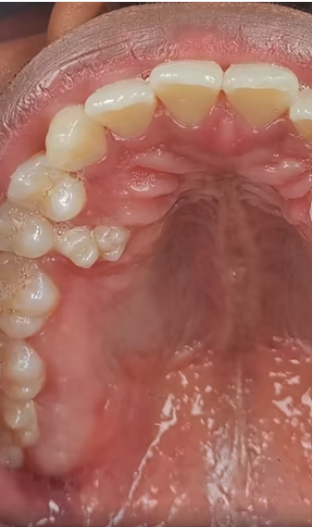

اعترفت موسوعة جينيس للأرقام القياسية برجل ماليزي بسبب فمه الذي يحتوي على 42 سنًا، أي أكثر بعشرة أسنان من الشخص العادي.

وأشار الماليزي إلى أن صورة الأشعة السينية للأسنان أظهرت لاحقًا وجود أربعة أسنان أخرى لم تظهر بعد، وبحلول أوائل عام 2023، أدرك أن لديه 42 سنًا إجمالًا، لافتًا إلى أنه لحسن الحظ، نمت معظم الأسنان بشكل مستقيم ودون أي مضاعفات.

كما لفت مونياندي إلى إن أسنانه الزائدة لا تسبب له أي مشكلة، ومعظم الناس لا يلاحظونها حتى يذكرها، مضيفًا: "عادة ما يكون الناس متفاجئين للغاية ويجدون صعوبة في التصديق في البداية، خاصة عندما يعلمون أن لدي 10 أسنان أكثر من الشخص العادي، الذي يمتلك عادةً 32 سنًا".

حصل مونياندي رسميًا على لقب صاحب أكبر عدد من الأسنان في فم شخص (ذكر) أما الرقم القياسي النسائي فتحمله كالبانا بالان من الهند، التي تمتلك 38 سنًا